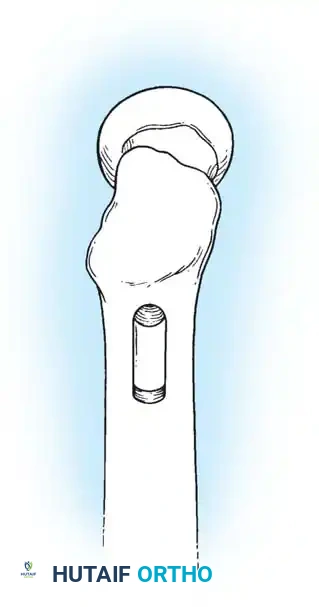

4. Reaming and Lag Screw Insertion

Once the guide wire is perfectly positioned, the lateral cortex is opened, and the femoral neck is reamed over the wire.

Reaming of the femoral neck and head over the precisely placed guide wire, preparing the channel for the lag screw.

The lag screw is then inserted. It is crucial not to over-insert the screw, which can penetrate the articular cartilage, nor to under-insert it, which compromises fixation.